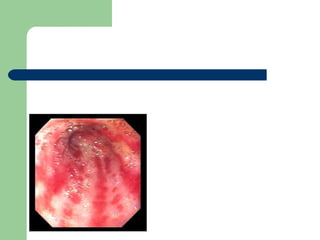

Gastritis Diffuse gastritis .   Erosions  are usually  multiple  and found primarily in the fundus and body of the stomach.  Chronic slow  bleeds are most commonly associated with  H. pylori Brisk Bleeding : ingested substances as NSAIDs, alcohol, steroids, or other drugs.

Gastritis Diffuse gastritis. Erosions are usually multiple and found primarily in the fundus and body of the stomach. Chronic slow bleeds are most commonly associated with H. pylori Brisk Bleeding : ingested substances as NSAIDs, alcohol, steroids, or other drugs.